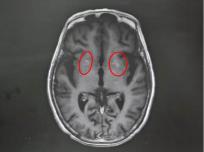

该院神经内一科副主任匡祖颖接诊后,详细询问病史并进行查体,结合影像检查结果,迅速锁定了病因——非酮症高血糖性偏侧舞蹈症。影像显示,王奶奶的双侧基底节区出现异常信号。进一步追问得知,她两年前查出高血糖,但一直没有规律服药,往往只在自我感觉血糖升高时才吃一点降糖药。这次入院后测出的空腹血糖高达13mmol/L,餐后血糖更达到21mmol/L,是正常值的两倍。匡祖颖解释,这种病多见于血糖控制不佳的人群,核心诱因正是长期严重的高血糖“烧坏”了大脑深部的纹状体。